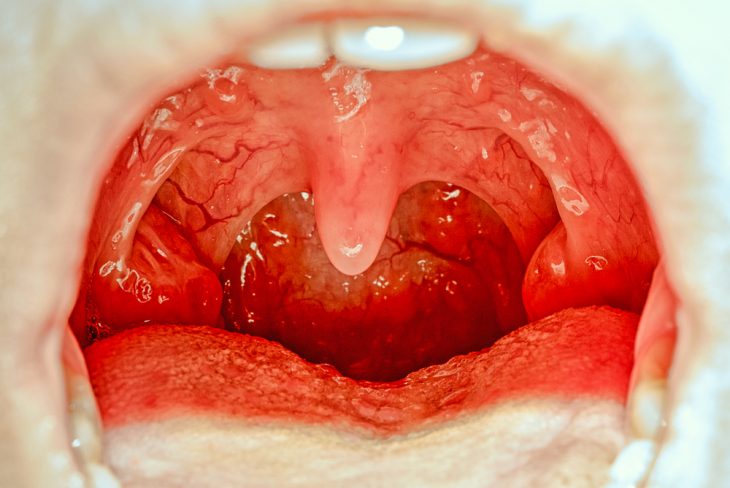

Бактериальная ангина достаточно часто характеризуется покраснением горла, увеличением миндалин в размере и появлением на них гнойников (лакунарная и фолликулярная форма заболевания). В некоторых случаях поверхность слизистой оболочки изъязвляется (язвенно-некротическая форма), покрывается серым или желто-зеленым налетом, возникают очаги некроза. Как правило, миндалины набухают, увеличиваются в размерах, и глотание становится болезненным, что может привести к отказу больного от приема пищи. Для бактериальной ангины типично двухстороннее поражение миндалин, сопровождающееся общими симптомами наличия инфекции – слабостью, повышенной утомляемостью, высокой температурой.

Кандидоз ротоглотки – это воспаление миндалин без температуры и сильного нарушения общего самочувствия. Местные симптомы: на поверхности миндалин, язычка, небных дужек заметен творожистый легко снимающийся налет.

Дифтерия. Классическая ангина при дифтерии сопровождается появлением трудно отделяемых на поверхности миндалин пленок, которые могут распространяться на мягкое небо и дужки.

Другие болезни. Воспаление миндалины, с одной стороны, часто наблюдается при сифилисе и туляремии. Скарлатина характеризуется яркой, «пылающей», гиперемией слизистой оболочки миндалин и глотки. Тонзиллит при лейкозе и других заболеваниях крови имеет различную симптоматику и зависит от характера присоединения вторичной инфекции.